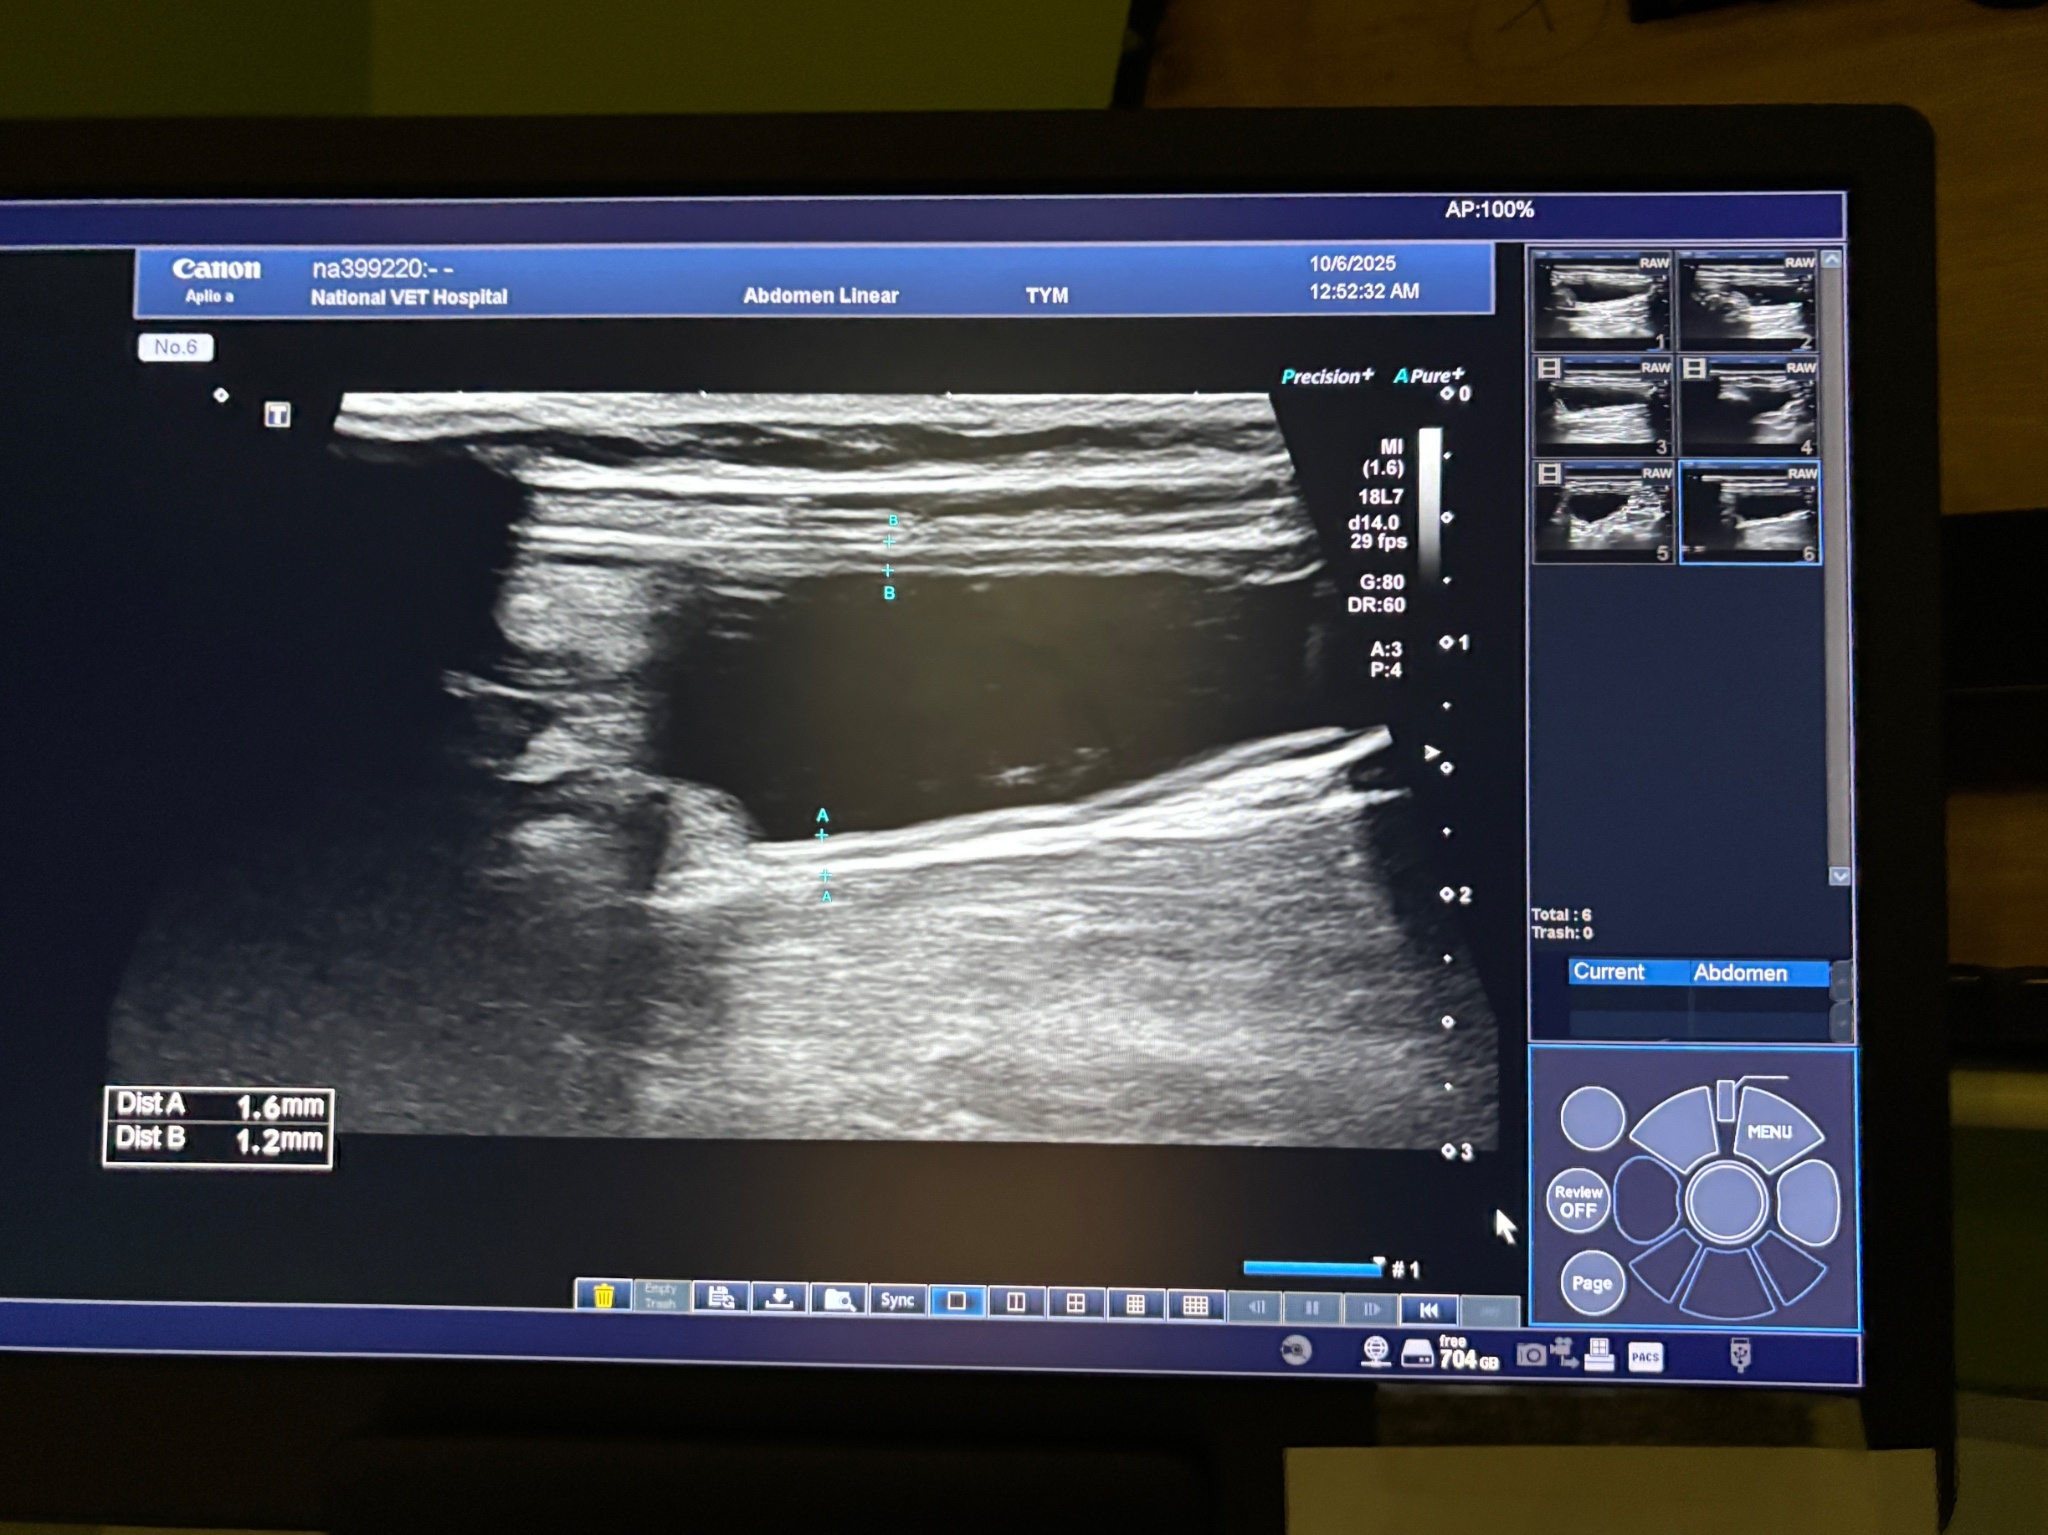

深夜讓給大家看皮蛋🐱 尿尿的地方

剛剛會去複診結束✔️ 膀胱發炎恢復正常了🥹

但裡面還有一點點結石細砂,現在就是繼續吃處方飼料(溶解結石)